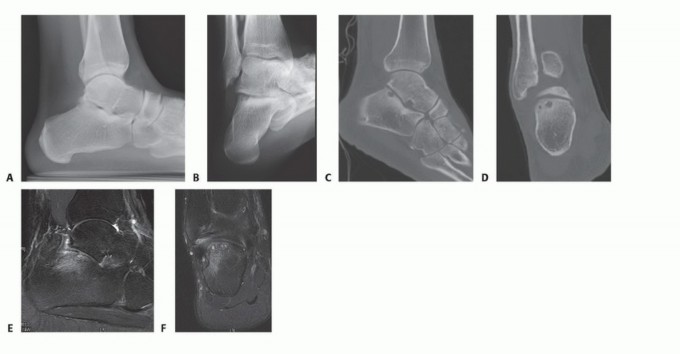

DEFINITION Lateral or posterior subtalar arthroscopy confers diagnostic and potentially therapeutic value in …